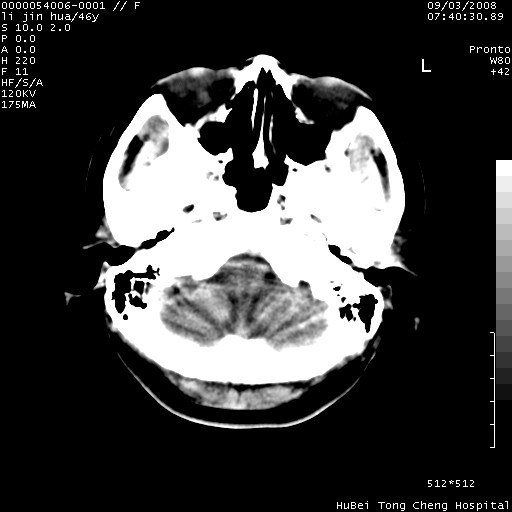

以下是引用panyishengct在2008-9-6 1:47:00的发言:[br]病史?[br]左侧枕/顶叶见一等/低混杂密度占位,壁完整,厚薄较均匀,其前方似有一类似小病灶,周围有水肿带,请结合病史考虑,脓肿可能,不排外转移瘤或胶质瘤,建议增强扫描。